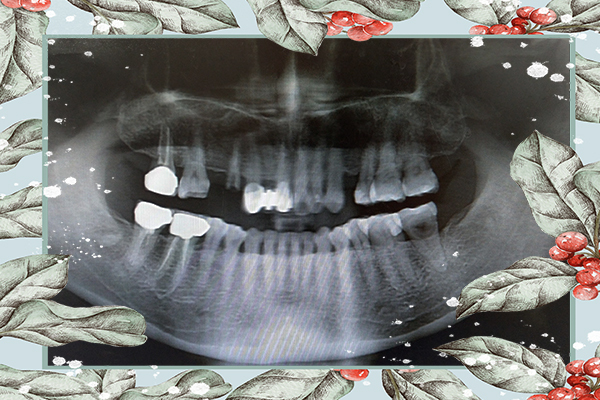

林義城醫師在看完小玥奶奶的斷層掃描後

很仔細在跟我們討論植牙療程

告訴我們哪種植體對奶奶來說比較牢固阿

應該要怎麼做植牙手術比較不用痛那麼久阿